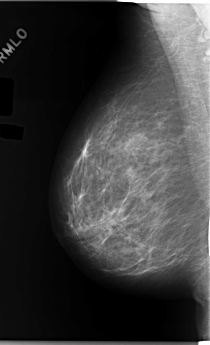

C_0170_1.RIGHT_MLO

LEFT_MLO LINES 5952 PIXELS_PER_LINE 3264 BITS_PER_PIXEL 12 RESOLUTION 50 OVERLAY